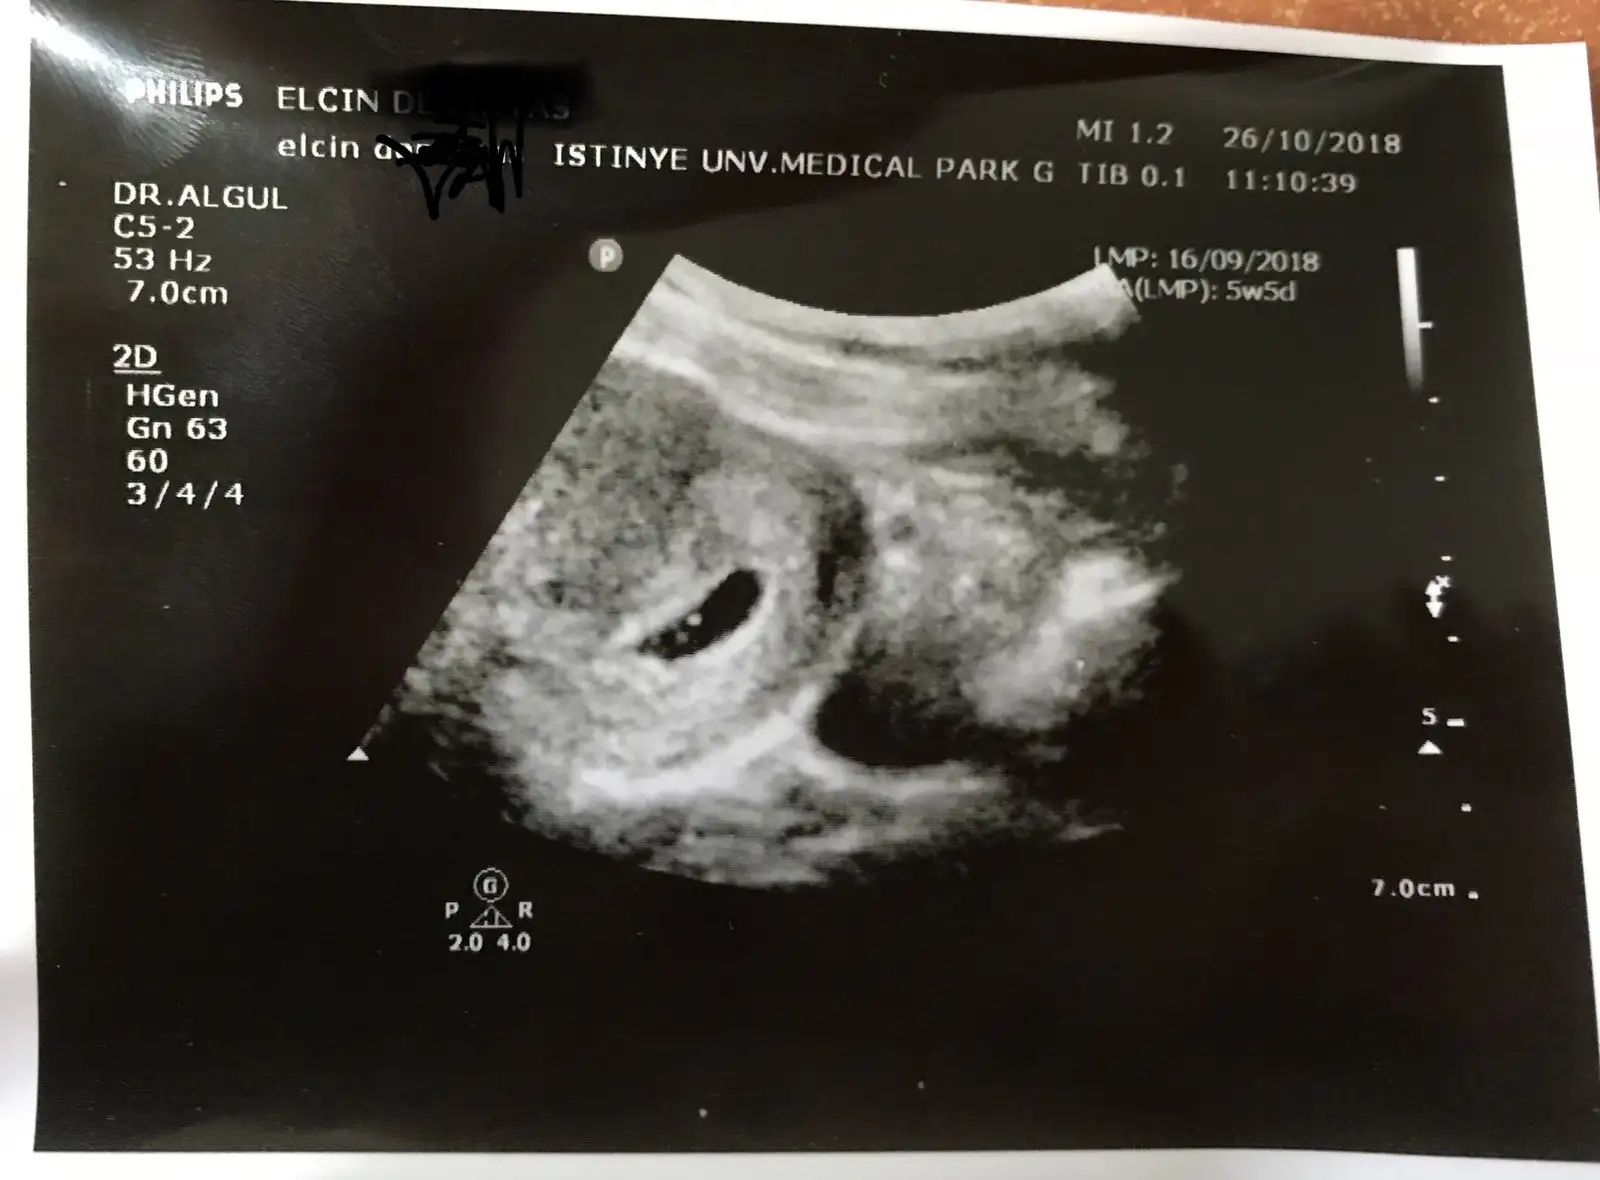

Benım 5+4 de gözüktü canım senin kaç olcak ozman ?ahahaha tamam ilk gebelik tecrübesizliği olduğu kanısını koydum şuan

5+4 olcak benim de.Benım 5+4 de gözüktü canım senin kaç olcak ozman ?

İçinde bebeğide görmüştük

4+4 de gittiğiöde birley göremedi sadece rahım kalınlaşmasını gördü

ayyy pardon ya 4+4Benım 5+4 de gözüktü canım senin kaç olcak ozman ?

Gittim ben 4+4 de ilk randevum kadın demişti hiçbirşey göremicez ama gelin bi bakalım demişti .

Karından baktı rahım duvarı kalındı onu gösterdi bak rahmın gebeliğe hazırlanıyor demişti .

Alttan bakmadı . Pek sevmıyordu sağolsun :))